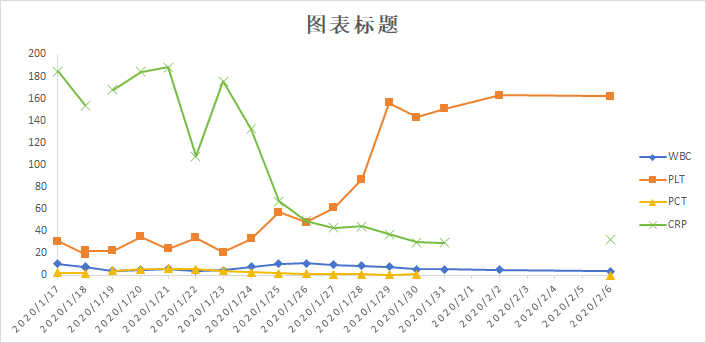

入室诊断:发热查因:结节病?腹膜炎,肺部感染。处理措施包括应用抗生素前行病原学检查;暂予泰能及替考拉宁抗感染,并加强支持治疗。但病情改善不明显。入院第4天(2020-01-21)收到血及腹水培养结果:马尔尼菲篮状菌。修正诊断:马尔尼菲篮状菌感染;肺部感染;腹腔感染;肝功能损伤;胸腔积液;腹腔积液。立即给予两性霉素B治疗。首剂15 mg, 每日增加5 mg, 第4日30 mg, 同时患者热退,胸腹腔积液减少,肝功能好转,凝血功能紊乱纠正,PLT稳步提高。2020-01-31转到呼吸科进一步治疗,两性霉素B疗程满2周,累计量480 mg后序贯伊曲康唑口服治疗,治疗12 d后纵膈淋巴结缩小,患者痊愈出院,出院前CT检查见图 4,WBC等指标变化见图 5。

| 图 5 诊治过程中WBC、PLT、PCT、CRP变化趋势 |